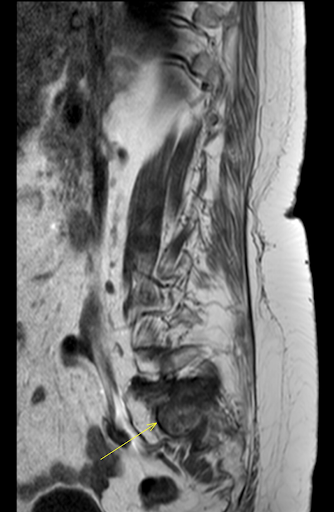

Figura 4: RMN arătând fractură de insuficiență sacrală pe fond de osteoporoză și paratiroidectomie

the msk playbook spinal insufficiency fractures

Figura 5: RMN arătând fractură de insuficiență sacrală pe fond de osteoporoză și paratiroidectomie

Figura 6: RMN arătând fractură de insuficiență sacrală pe fond de osteoporoză și paratiroidectomie